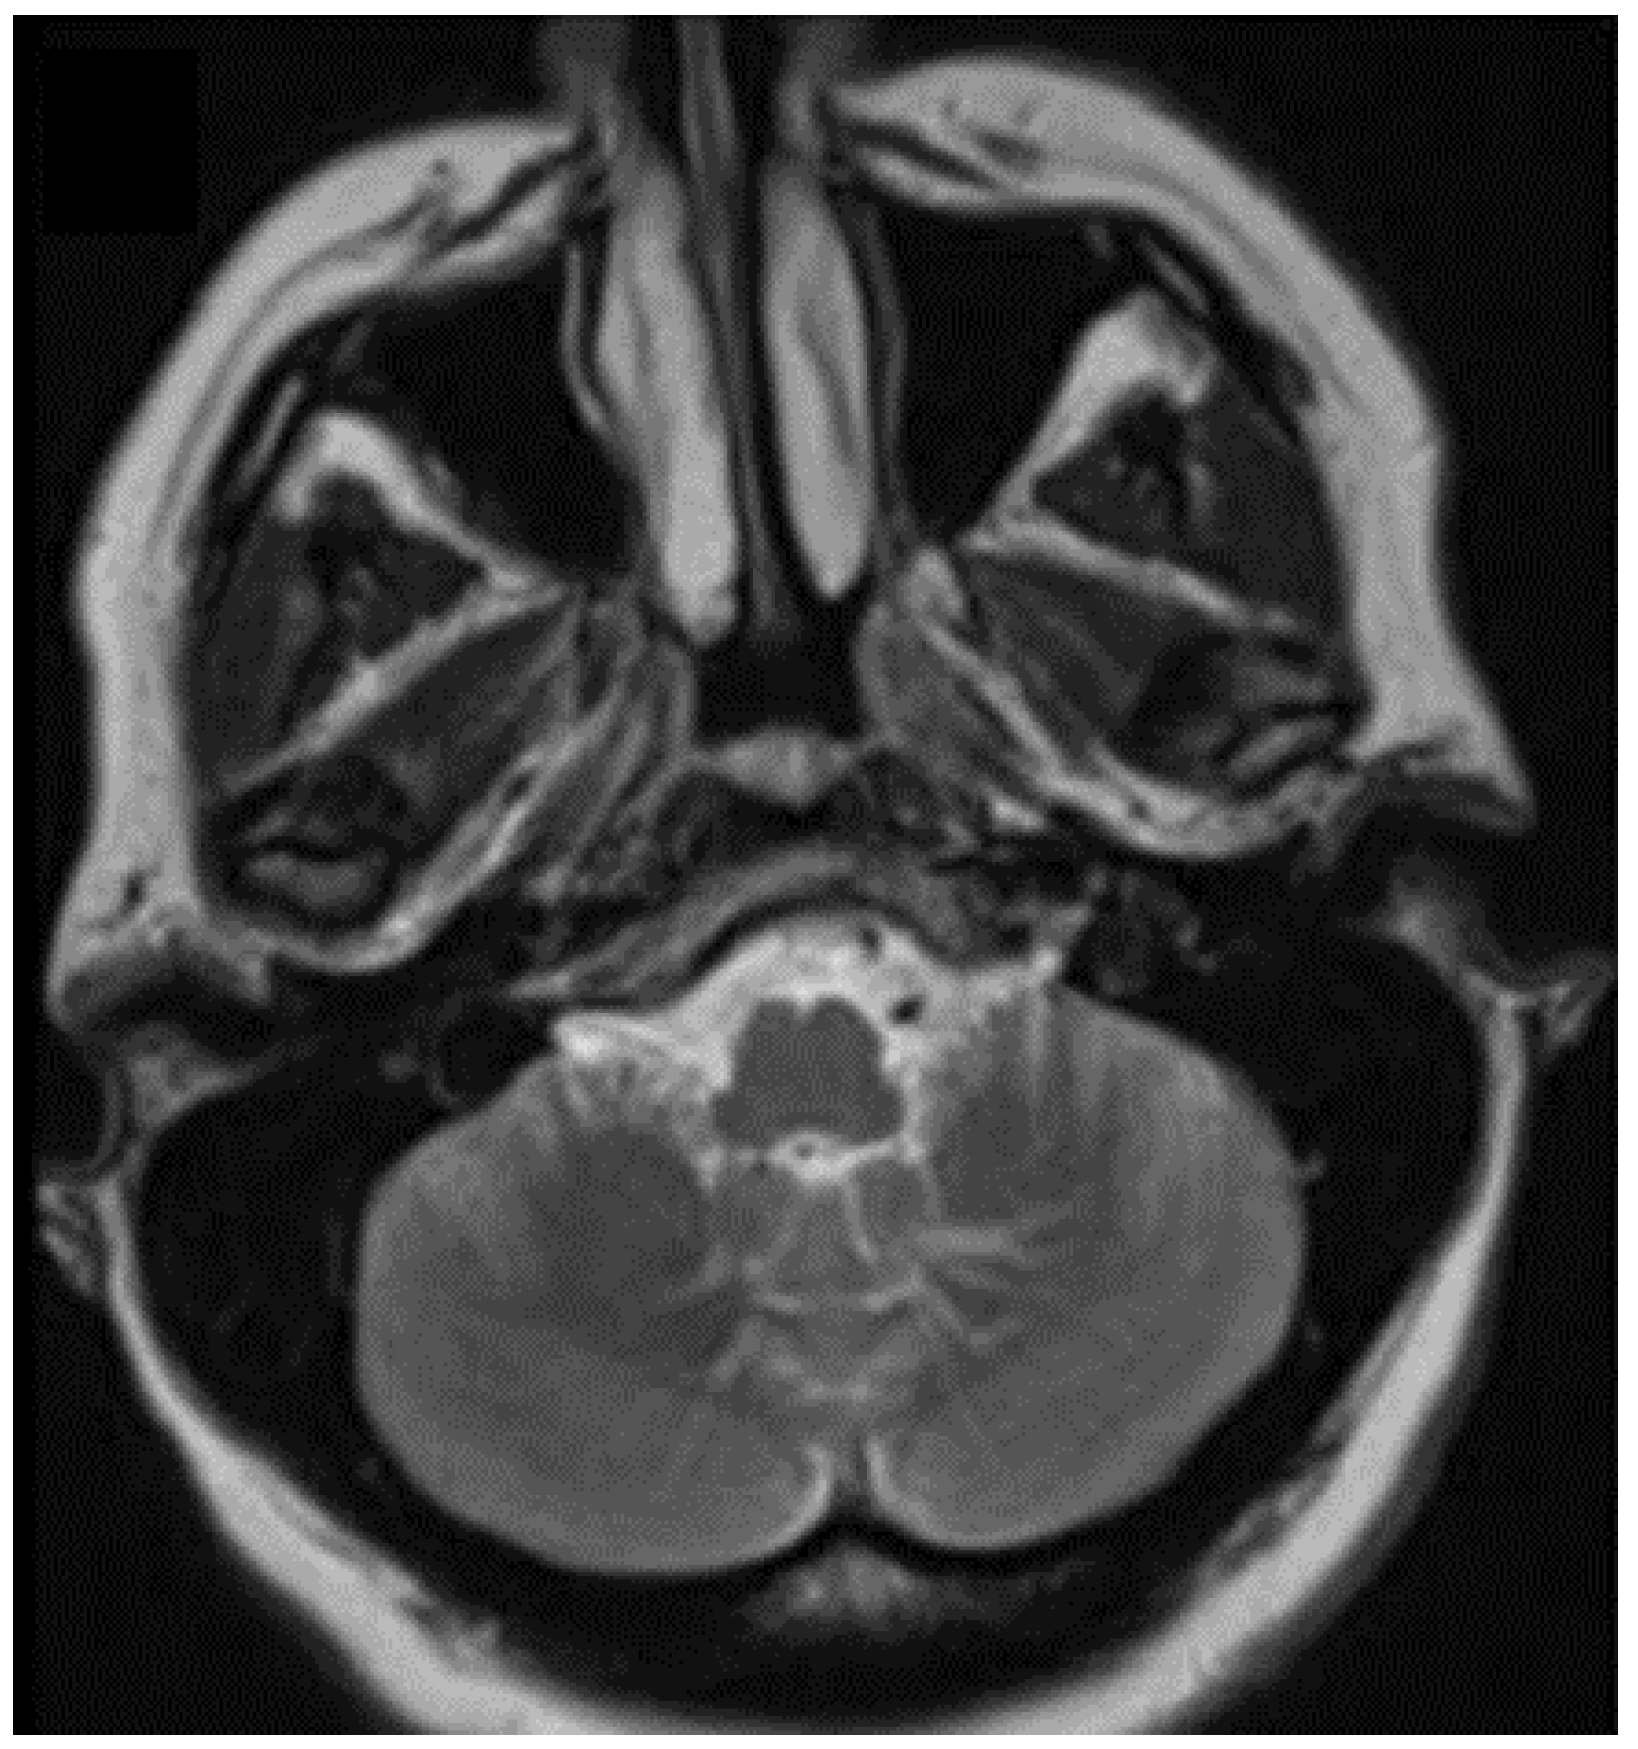

3.1.2. Brain Cavernous Angiomas

- Ebrahimzadeh, K.; Tavassol, H.H.; Mousavinejad, S.A.; Ansari, M.; Kazemi, R.; Bahrami-Motlagh, H.; Jalili Khoshnoud, R.; Sharifi, G.; Samadian, M.; Rezaei, O. The Sensorineural Hearing Loss Related to a Rare Infratentorial Developmental Venous Angioma: A Case Report and Review of Literature. J. Neurol. Surg. A Cent. Eur. Neurosurg. 2021. [Google Scholar] [CrossRef]